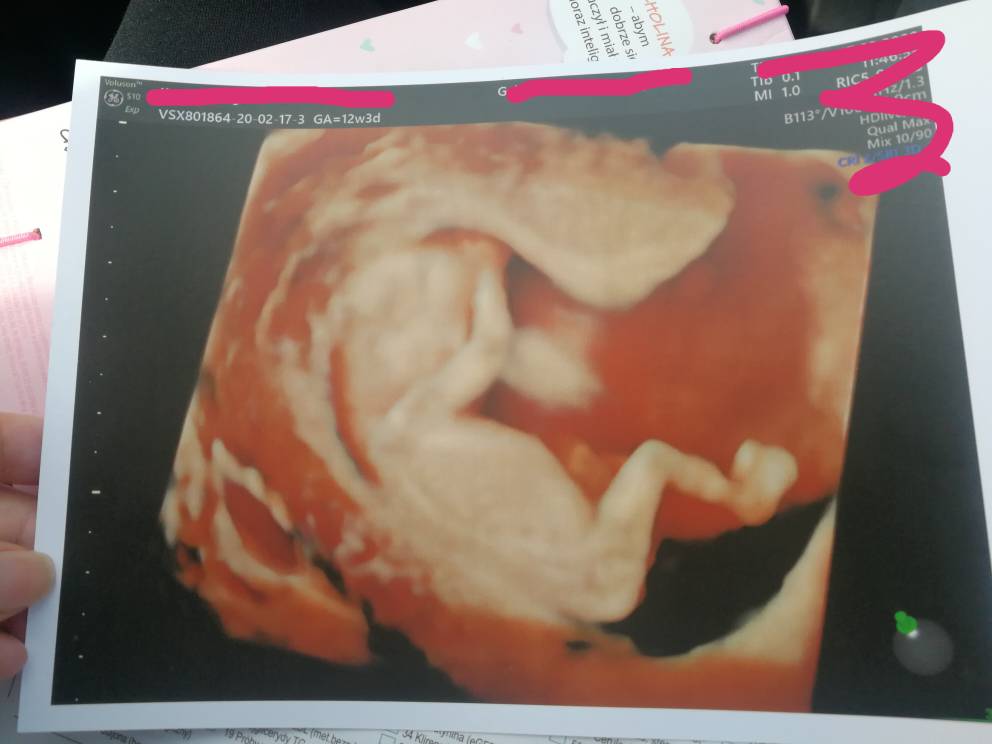

A to moje maleństwo z pn (12+3), dxidziol nie chciał współpracować.. Wykryto Arse, za 3 dni następne usg genetyczne.

Załączniki

• IMG_20200217_120347.jpeg

IMG_20200217_120347.jpeg

45,7 KB · Wyświetleń: 113

• IMG_20200220_080222.jpeg

IMG_20200220_080222.jpeg

45,3 KB · Wyświetleń: 189

Błądząca tętnica prawa podobojczykowa... Ma to coś związane z przełykiem.. Być może z wada serduszka.. Tak naprawdę w internecie nic nie można konkretnego znaleźć, mam nadzieję że dowiem się w pn coś wiecej po kolejnym usg. Jest markerem zespołu downa też podobno... Chociaż u nas to jedyna nieprawidłowość. Trzymajcie kciuki